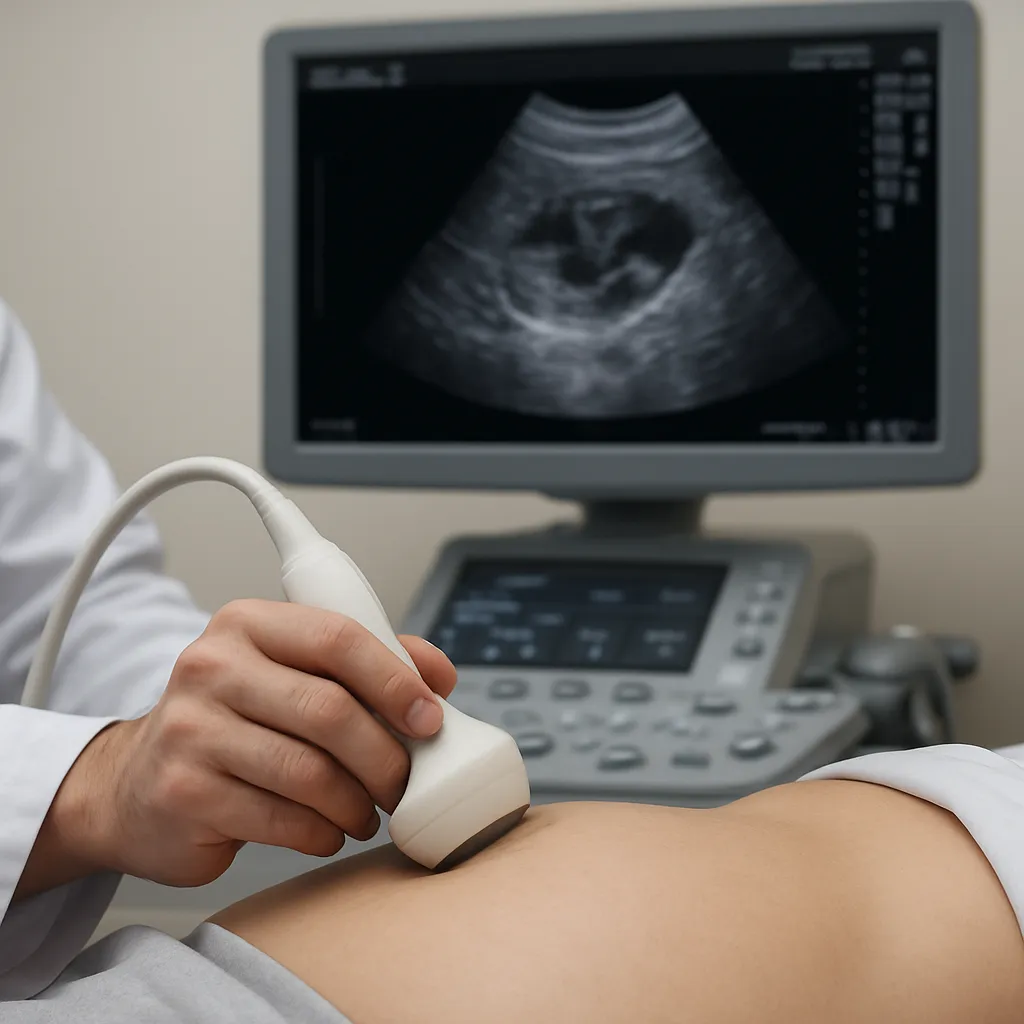

Ultrasonografia, zwana często ultrasonografią lub USG, bazuje na falach dźwiękowych o wysokiej częstotliwości. Emisja i odbiór fal następuje za pomocą sondy, co pozwala uzyskać obraz narządu w czasie rzeczywistym. Badanie spełnia kryteria bezpiecznej, nieinwazyjnej i szeroko dostępnej metody. Dzięki zastosowaniu różnych głowic możliwe jest dokładne zobrazowanie nerki, miedniczki nerkowej, moczowodów oraz sąsiadujących struktur anatomicznych.

Ultrasonografia stanowi pierwszą linię diagnostyki kamicy moczowej. USG jest szczególnie przydatne w identyfikacji złogów o średnicy powyżej 3–4 mm. Dzięki badaniu można ocenić:

Na obrazie USG kamień moczowy prezentuje się jako jasny, echogeniczny punkt z towarzyszącym cieniem akustycznym. Stopień cienia jest proporcjonalny do gęstości złogu. W raporcie sonograficznym powinny znaleźć się informacje o: